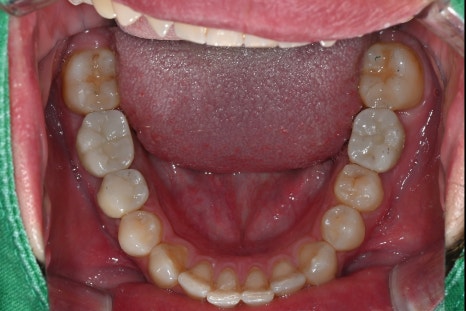

These are intraoral photos of the upper and lower teeth taken at the time of the visit.

Due to the loss of the second small molar on the upper right, implant treatment was needed.